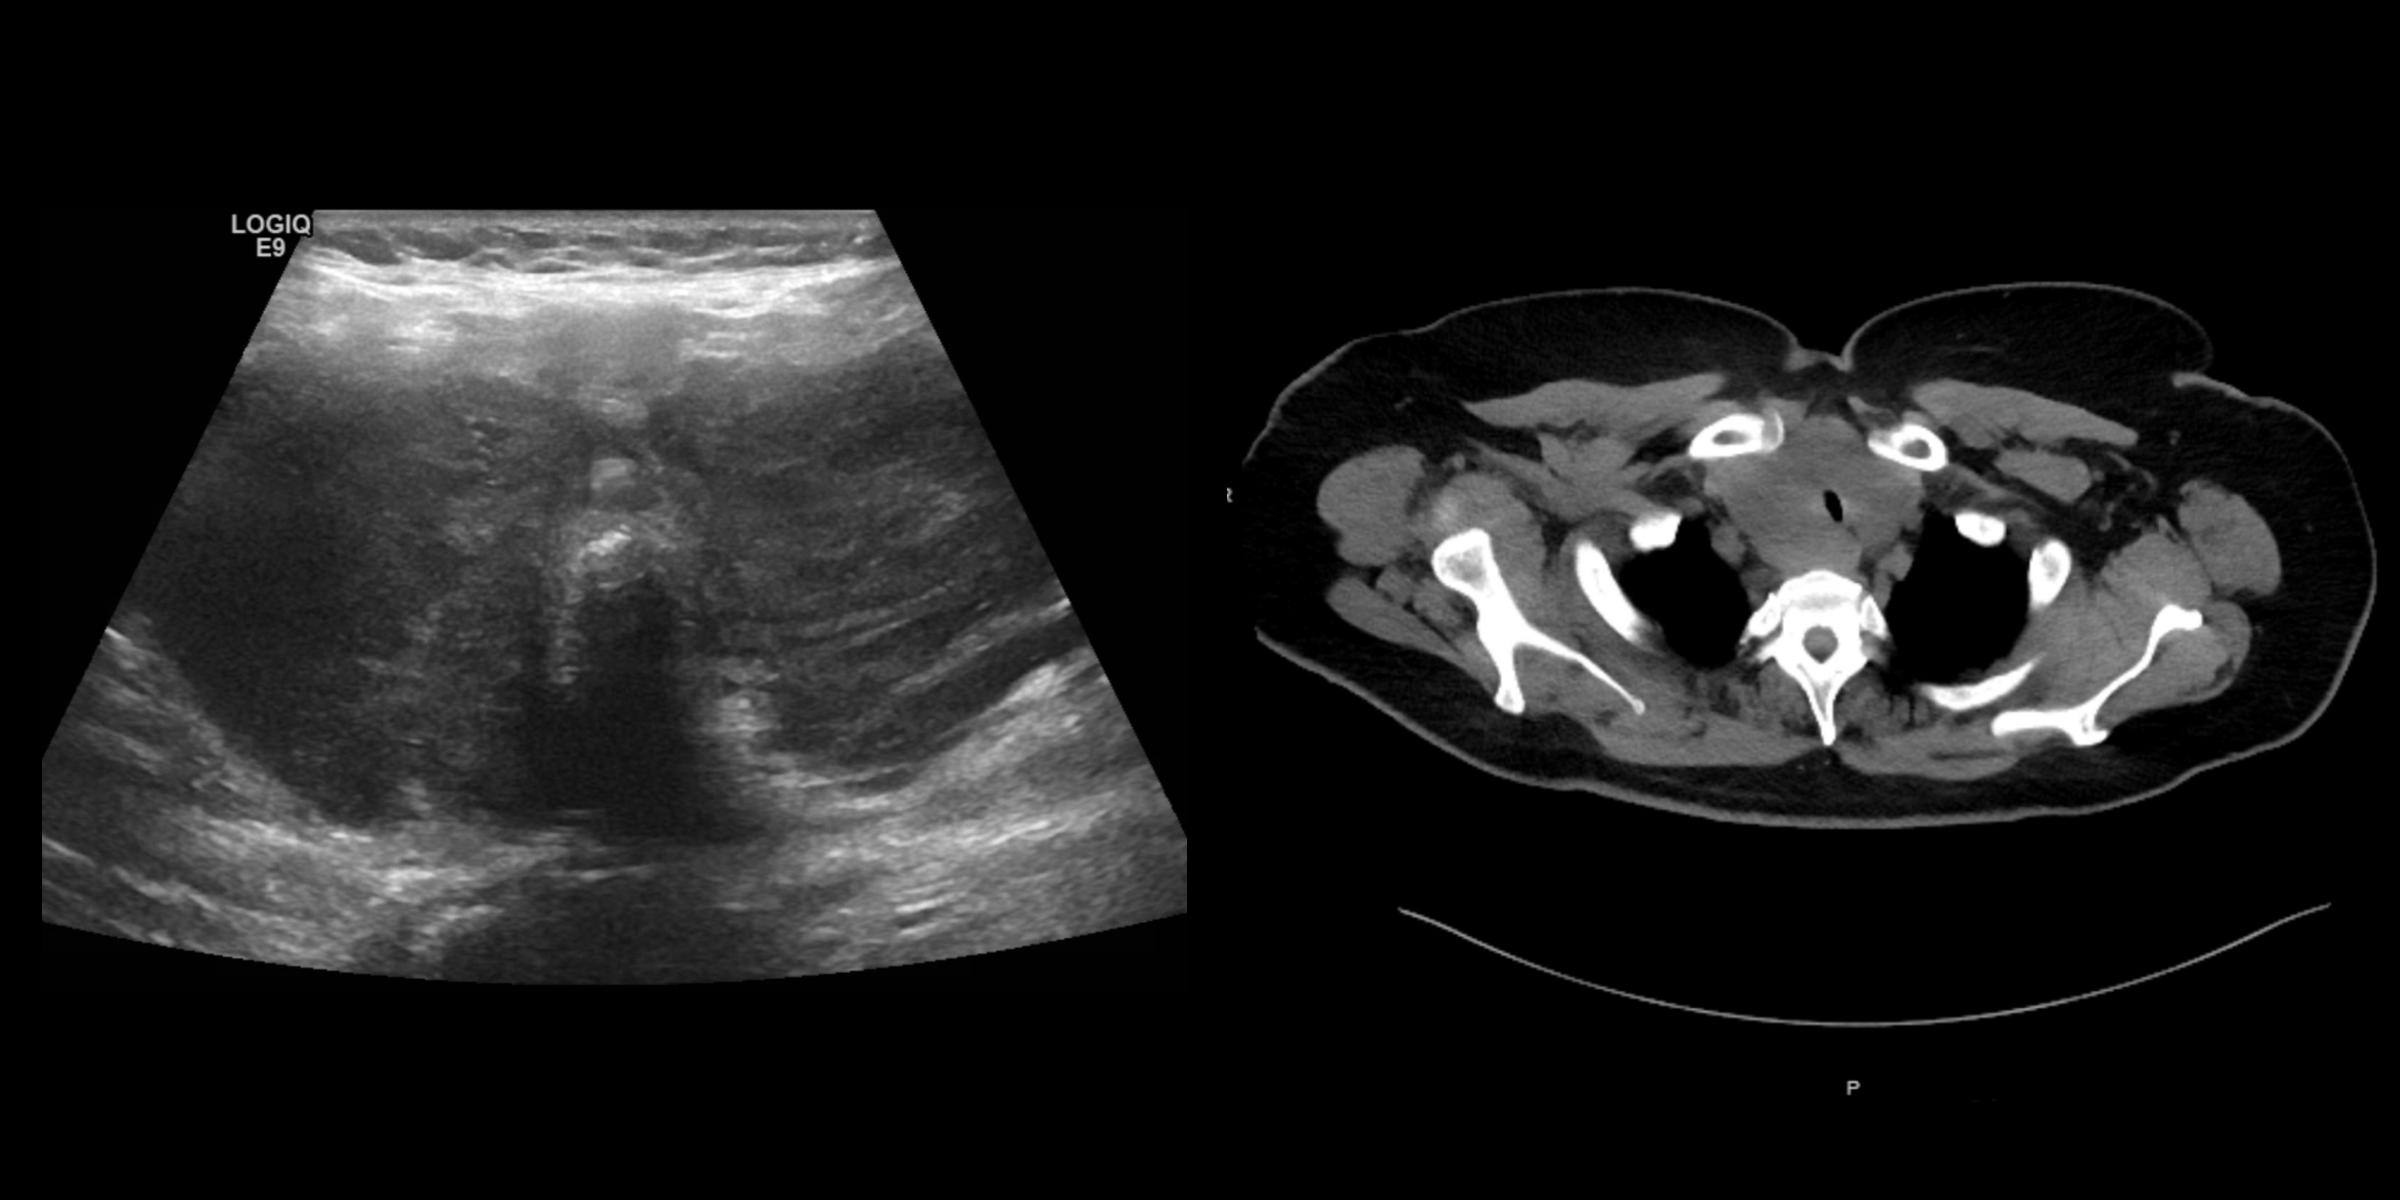

A 61-year-old woman presented to the hospital with dysphagia to solid foods and dyspnea on exertion that has been worsening over the last 1-2 months. Past medical history includes hypothyroidism from Hashimoto’s thyroiditis on levothyroxine, and T2DM on metformin (well-controlled). Physical exam is notable for significant diffuse thyroid enlargement, not rock hard or tender thyroid, positive Pemberton’s sign, hoarse voice (but she is able to speak in full sentences). Biochemical testing revealed normal CBC, CMP, and a TSH of 5.02 uIU/mL (normal 0.5-5.7). Thyroid ultrasound and neck CT are shown below.

This patient, with a history of Hashimoto’s thyroiditis, presents with a rapidly enlarging thyroid mass that has caused dysphagia and dyspnea on exertion. In that clinical context, the most likely etiology of her symptoms is thyroid lymphoma, and the most common type of primary thyroid lymphoma is diffuse large B-cell lymphoma (DLBCL). Thyroid lymphoma is a rare malignancy representing less than 5% of all thyroid cancers. Hashimoto’s thyroiditis is a well-established risk factor, as patients with Hashimoto’s thyroiditis have a 60 times higher risk of developing primary thyroid lymphoma, compared to the general population. On ultrasound, thyroid lymphoma will appear with diffuse enlargement of the thyroid in a uniform and very hypoechoic pattern, like the one presented here. Usually cross-sectional imaging will be needed, and in this case, there was the apparent narrowing of the upper trachea.